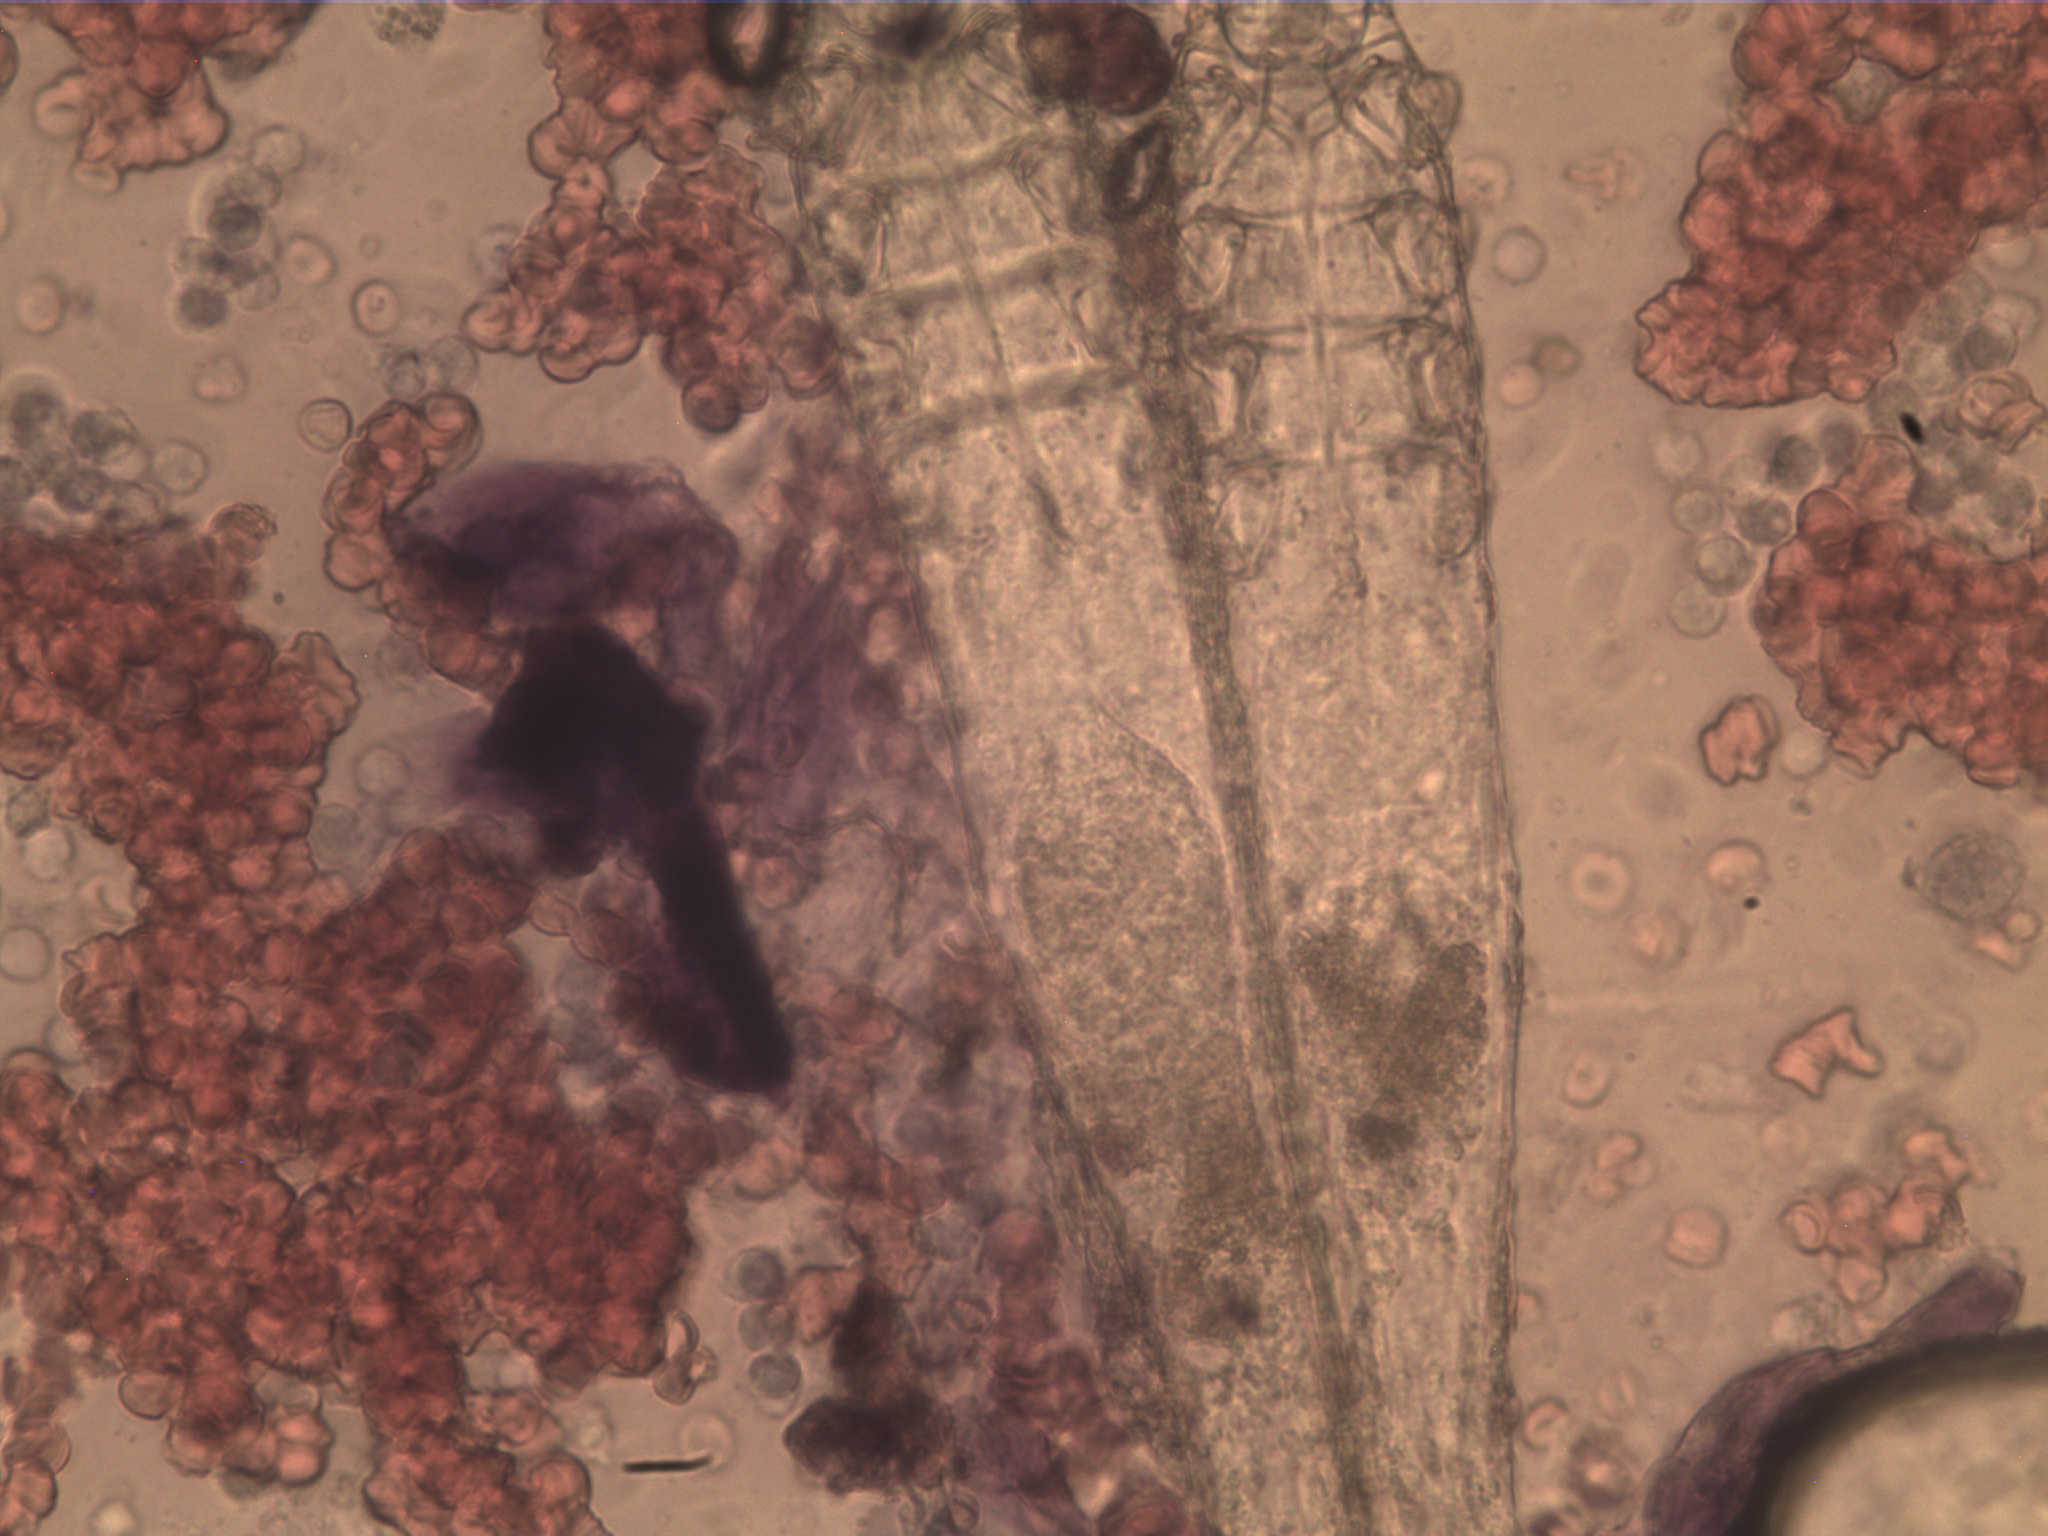

一例藏獒蠕形螨伴发脓皮病的诊断治疗

藏獒大红系青海玉树名门之后,主人千辛万苦迎接回阜阳老家,刚一个多月,发现大红全身起红疙瘩,腹侧四肢皮肤化脓溃烂并夹杂恶臭,当地兽医治疗一周不见好转,并出现恶化情况,不吃食物,烦躁不安,对人有攻击性;主人经过熟人介绍转院至我处,经过本院皮肤取样染色显微镜检查确诊系蠕形螨伴发球菌感染造成脓皮病,如图经过确诊治疗一周后明显好转,藏獒是蠕形螨的高发品种,蠕形螨主要在毛囊内繁殖生活,造成毛囊炎后引起皮肤感染。治疗首先控制感染,驱杀螨虫,增加皮肤免疫力防止复发。定期复查。